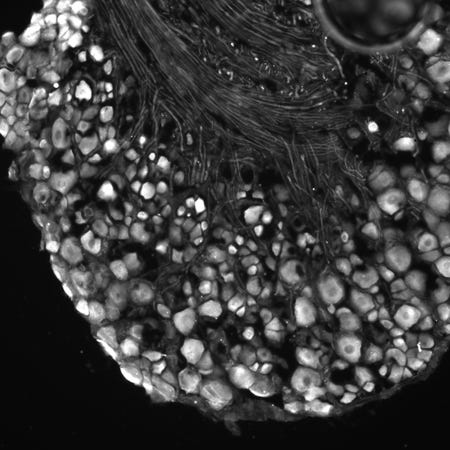

Macrofagen zijn afweercellen die ziekteverwekkers aanvallen en opeten. “Sinds enige tijd weten we dat deze cellen nog veel meer taken hebben”, vertelt Eijkelkamp. “Ze spelen ook een rol bij het uitschakelen van pijn.” De onderzoekers ontdekten dat macrofagen mitochondriën (de ‘energiefabriekjes’ van de cel) aan zenuwcellen kunnen afgeven. Deze zenuwcellen geven pijnsignalen vanuit het ontstoken weefsel door, en dat is waarom iemand pijn voelt. “We ontdekten dat het afgeven van mitochondriën helpt bij het stoppen van de pijn”, aldus Eijkelkamp.